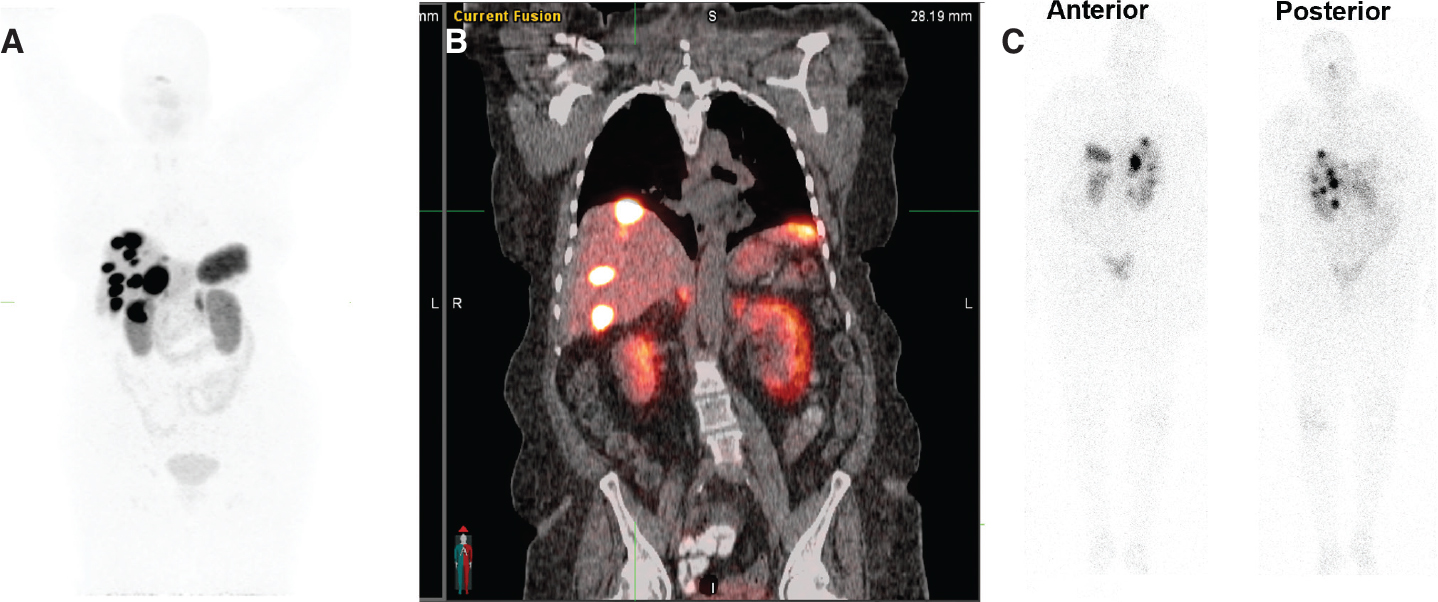

Radiation safety precautions for patients after receiving 177Lu-DOTATATE therapy are to restrict the dose received by patients’ family members to less than 5 mSv in 5 years and to members of the public to less than 1 mSv per year. Patients receive oral and written radiation safety precautions for three days after receiving therapy. Blood and urine are the main sources of contamination during and after radionuclide administration. 177Lu-DOTATATE is excreted primarily in urine, therefore, the foremost focus for the first 3 days after therapy is to prevent urinary contamination (46). During this time, a double flush of the toilet is recommended after urination. Patients should wash their hands after using the bathroom. The RADAR website has an online tool that allows the calculation of cumulative doses to family members or members of the public from exposure to patients treated with 177Lu-DOTATATE (47). In addition to the beta particles, 177Lu-DOTATATE also emits two gamma rays (113 KeV and 208KeV) with low relative abundance (6.2% and 10.4% respectively) (48) (Figure 5).

Fig 5

Figure 5. 74-year-old female with advanced and inoperable metastatic ileal NET. A. 68Ga-DOTATATE MIP image and B. Fused coronal image show multiple intensely somatostatin receptor-rich tumors in the liver and portocaval lymph node. C. Post-therapy emission scan acquired 7 days after 117Lu-DOTATATE therapy (anterior and posterior images) Somatostatin receptor rich tumor in liver and a portocaval lymph node.